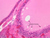

The thyroid gland (slide B-51, lead hematoxylin [10x, 20x, 40x, 40x]; B-52, H&E [10x-labeled, 20x, 40x-labeled, 40x]; B-53, PAS [2.5x, 10x, 20x, 40x]) consists of many closely packed, roughly spherical structures known as follicles, which are enclosed in a thick connective tissue capsule. Connective tissue septa extend from the capsule into the substance of the gland, carrying numerous blood vessels. Follicular cells are arranged as shells of simple cuboidal epithelium surrounding a gelatinous mass known as colloid. Look for a ring of epithelial cells around the homogeneous, pink-staining colloid. The cytoplasm of the follicular cells (principal cells) is faintly basophilic. The follicular cells secrete thyroglobulin, a glycoprotein, which is stored extracellularly in the colloid. In response to TSH, the follicular cells endocytose the colloid and hydrolyze it to form thyroxine. You can see where colloid has been resorbed because this process leaves small holes in the colloid adjacent to the follicular cells. These holes are known as resorption lacunae (B-52 [10x, 20x, 40xlabeled]). Very active follicles may exhibit a columnar epithelium and increased numbers of resorption lacunae. Between follicles, the stroma of the thyroid gland consists of a thin layer of connective tissue and a rich capillary network. Parafollicular cells (light cells or C cells) are located in the connective tissue between follicles or adjacent to follicular cells within follicles. When they lie within the follicular wall, the parafollicular cells do not reach the lumen. Parafollicular cells are slightly larger than the follicular cells and, in H & E preparations, have a more lightly stained cytoplasm (B-52, H&E [10x, 20x, 40x-labeled] [10x-labeled, 20x, 40x-labeled] [10x, 20x, 40x] [10x, 20x, 40x]; B-53, PAS [10x, 20x, 40x]). Parafollicular cells are readily identifiable in slide B-51 (stained with lead hematoxylin), where they appear as purplish-black structures in which the nuclei are difficult to discern (B-51 [10x, 20x, 40x-labeled]). These cells secrete calcitonin, which lowers serum calcium levels by inhibiting bone resorption and accelerating osteoid calcification.